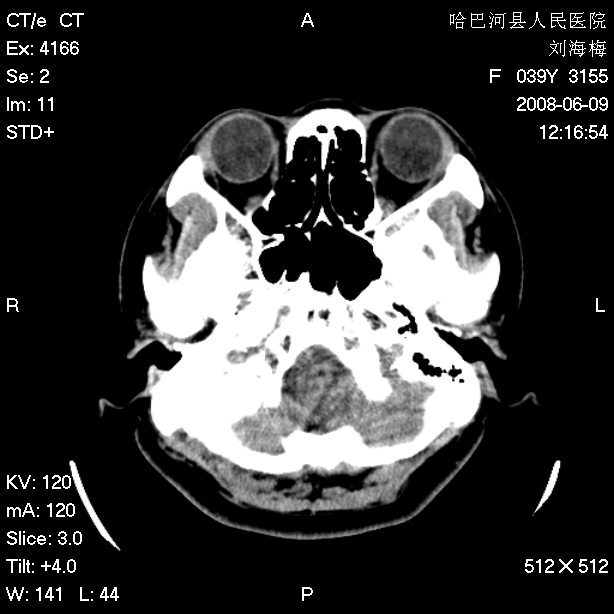

标题: CT13909:F39Y,头痛1年 [打印本页]

标题: CT13909:F39Y,头痛1年

头痛1年

嗜酸性肉芽肿?骨髓瘤?不像蛛网膜颗粒压迹,太大了,并且有占位效应。

支持枕骨蛛网膜颗粒压迹。头痛与此无关。

嗜酸性肉芽肿?骨髓瘤?不像蛛网膜颗粒压迹,太大了,并且有占位效应

支持枕骨胆脂瘤可能性最大。右侧乳突部密度增高,建议薄扫。